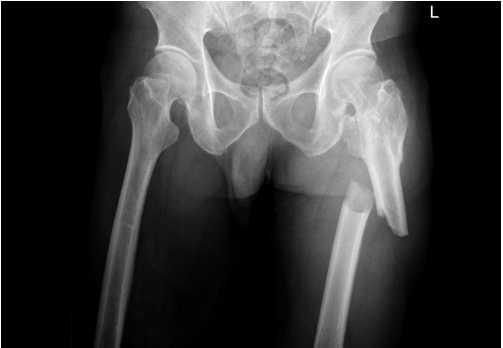

左圖:邱伯伯左側股骨骨折(大腿骨折),經過花蓮慈濟醫院麻醉團隊進行術前神經阻斷術、以及骨科團隊骨折固定手術(右圖)後,邱伯伯手術沒有了疼痛問題。